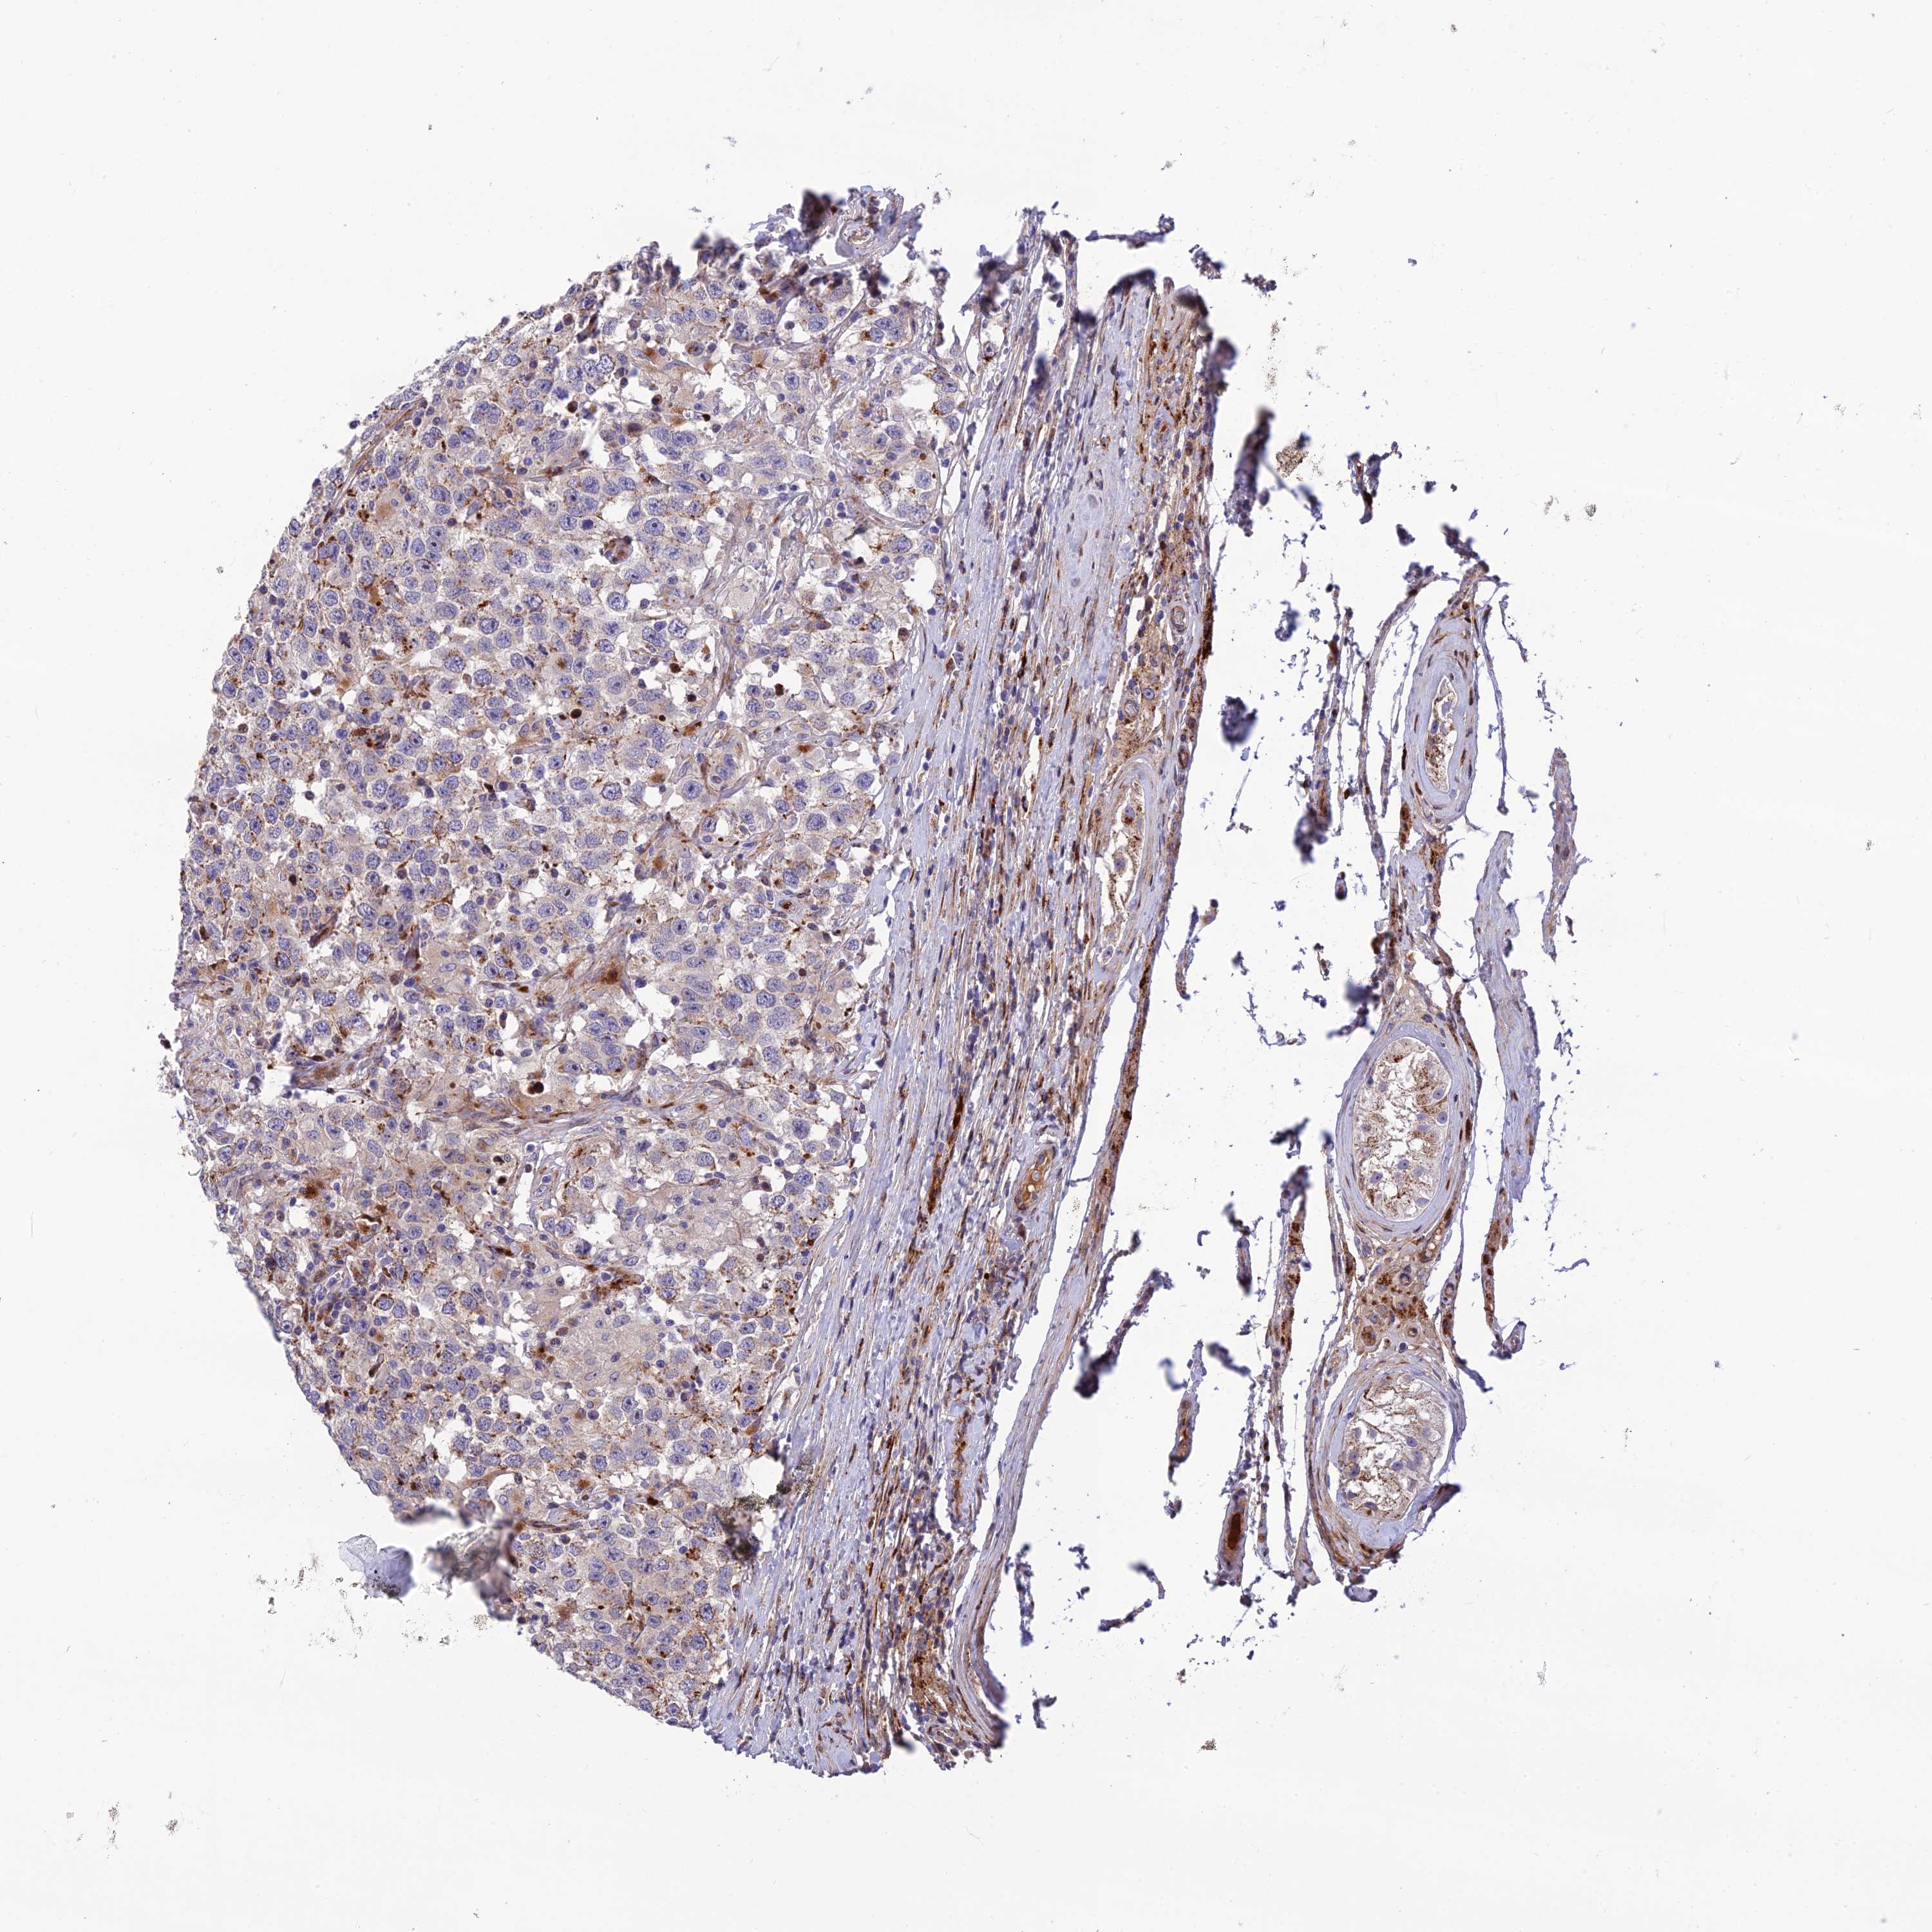

TESTIS CANCER - Protein expressioni

A mouse-over function shows sample information and annotation data. Click on an image to view it in a full screen mode. Samples can be filtered based on level of antibody staining by selecting one or several of the following categories: high, medium, low and not detected. The assay and annotation is described here.

Note that samples used for immunohistochemistry by the Human Protein Atlas do not correspond to samples in the TCGA dataset.

Antibody stainingi

Antibody staining in the annotated cell types in the current human tissue is reported as not detected, low, medium, or high, based on conventional immunohistochemistry profiling in selected tissues. This score is based on the combination of the staining intensity and fraction of stained cells.

Each image is clickable and will lead to virtual microscopy that enables deeper exploration of all samples and also displays staining intensity scores, fraction scores and subcellular localization as well as patient and tissue information for each sample.

Antibody HPA044047

Staining

High

Medium

Low

Not detected

Intensity

Strong

Moderate

Weak

Negative

Quantity

>75%

75%-25%

<25%

None

Location

Nuclear

Cytoplasmic/membranous

Cytoplasmic/membranous,nuclear

Carcinoma, Embryonal, NOS

Seminoma, NOS